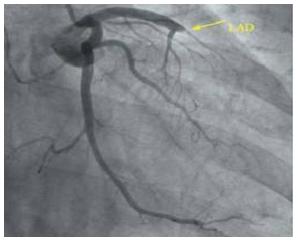

3.心脏超声能代替冠脉造影吗?

当然不能,心脏冠脉造影可是诊断冠心病的“金标准”,同样用房子做比喻,做造影是看房子的水管堵没堵,水管壁有没有生锈,需不需要疏通。而心脏超声不能显示冠状动脉全程。

(上图黄色箭头指示的地方这根“水管”闭塞了)